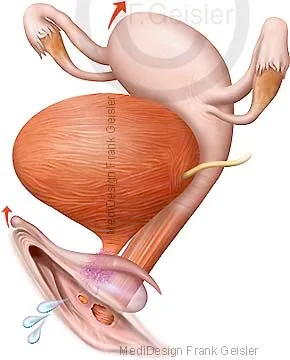

Geschlechtsorgane Gebärmutter Scheide Vulva der Frau; Uterus mit Eileiter Eierstock und Vagina

Der (Klitoris, Clitoris) der Frau ist ein aus Schwellkörpergewebe gebildeter Teil des weiblichen Genitals, der weiblichen Scham, das entwicklungsgeschichtlich dem Penis des Mannes entspricht. Die Klitoris ist ein erektiles Organ am oberen Ende der kleinen Schamlippen (Labia minora pudendi).

Das äußere Genitale beginnt in Höhe der Symphyse mit dem oberhalb der Schamspalte (Rima pudendi) liegenden Schamberg (Mons pubis). Nach unten und seitlich folgen die großen Schamlippen. Innen begrenzen die kleinen Schamlippen mit ihrer Innenfläche den Scheidenvorhof. Hier mündet wenig unterhalb der Klitoris (Kitzler) die weibliche Harnröhre in den Scheidenvorhof.